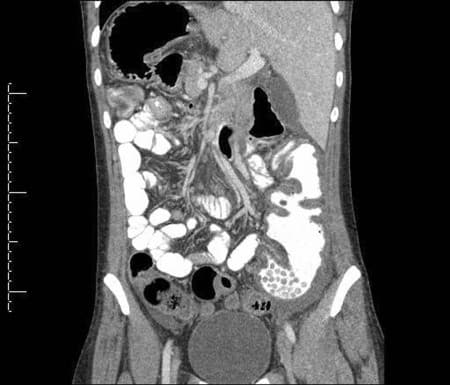

КТ органів черевної порожнини

Комп'ютерна томографія органів черевної порожнини — це сучасний неінвазивний метод діагностики, який дозволяє отримати детальні зображення внутрішніх органів за допомогою рентгенівського випромінювання.

Метод забезпечує високу точність діагностики захворювань печінки, жовчного міхура, підшлункової залози, нирок, селезінки та інших органів черевної порожнини.

Що показує КТ черевної порожнини?

Структуру та розміри печінки, підшлункової залози, селезінки

Стан жовчного міхура та жовчних проток

Нирки, сечоводи та сечовий міхур

Лімфатичні вузли черевної порожнини

Кровоносні судини (аорта, нижня порожниста вена)

Кишечник та інші органи травної системи

Кістки хребта та ребер

М'які тканини передньої черевної стінки